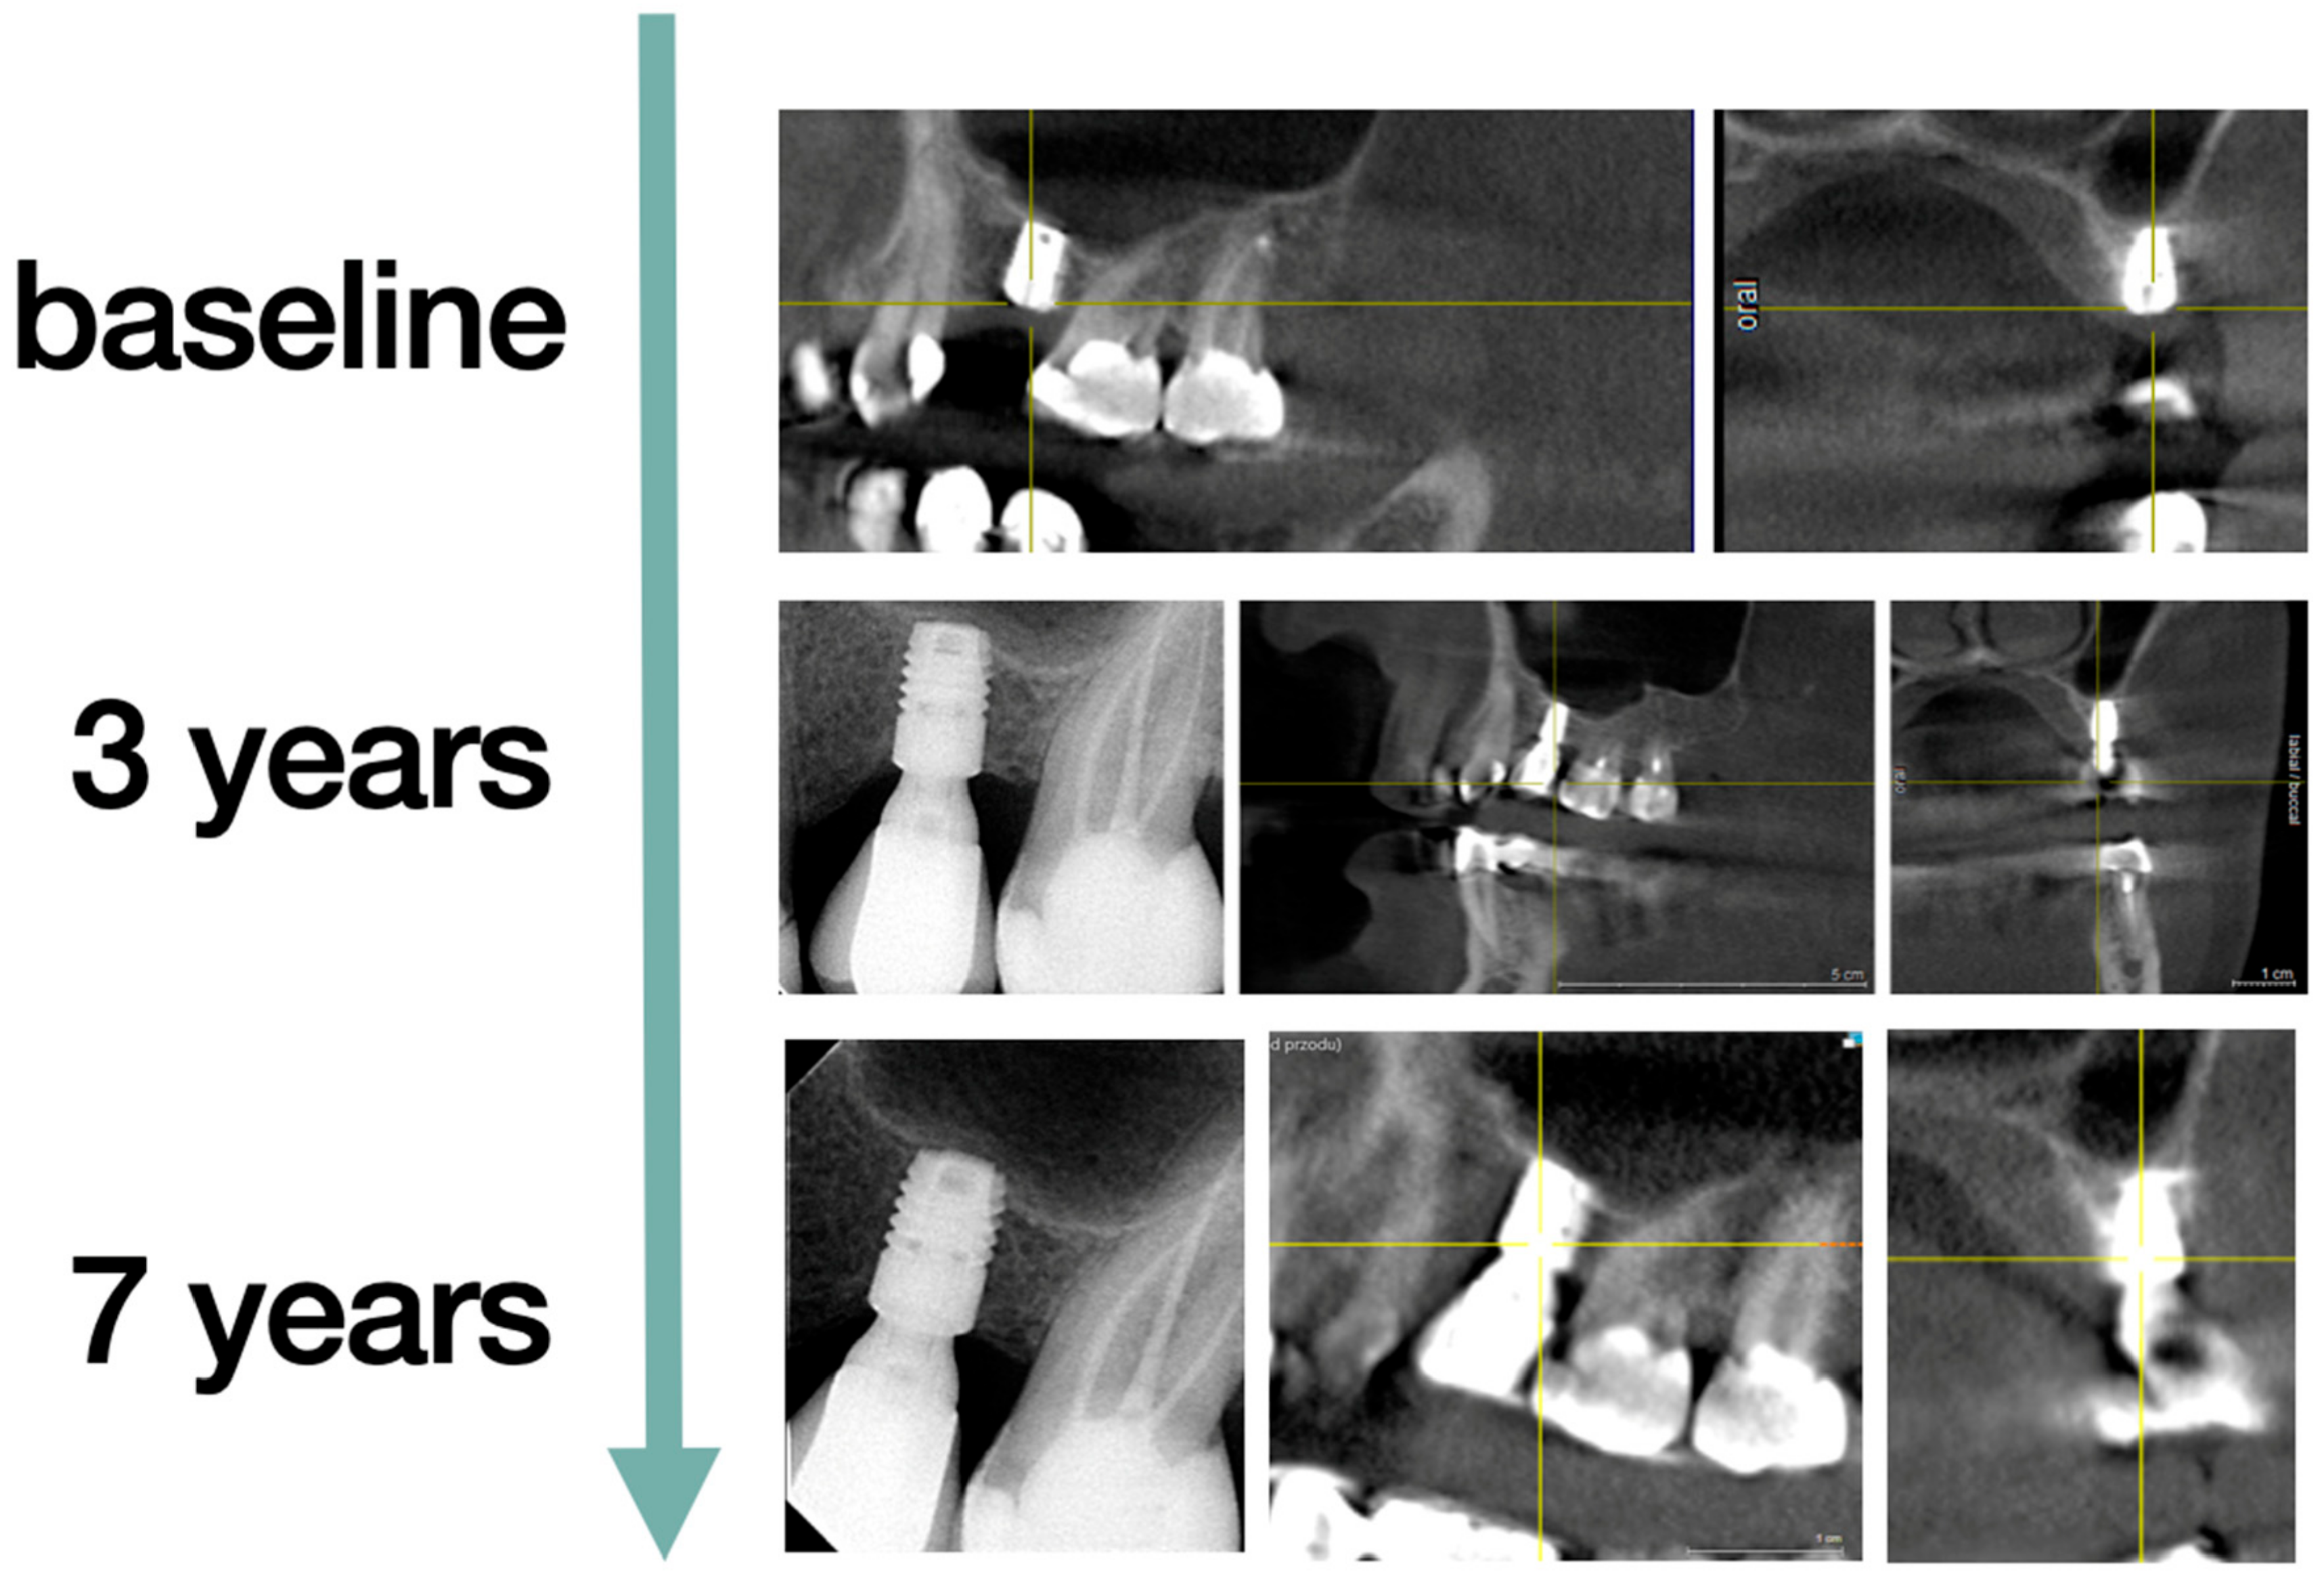

3.4. Marginal Bone Loss

3.5. Technical Complications